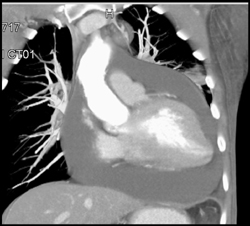

Wegener's of the Airway